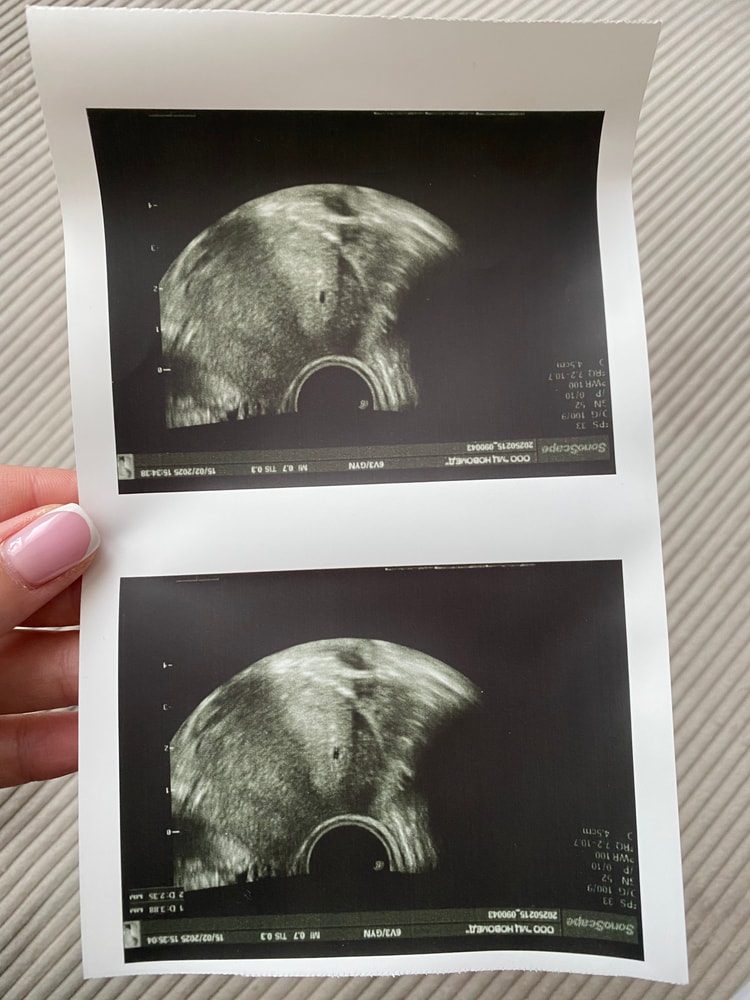

Уже кидала тут как-то свои тесты сегодня) кину еще раз Вот лично я тот человек, который так и не увидел сравнявшихся полосочек…все нервы помотала с этими тестами, не ярчали и все, первое время так и думала, что что-то не так, может замершая, может еще что. В итоге все хорошо, первый скрининг уже прошли) каков вывод? Не мотать себе зря нервы этими тестами. Показал беременность? Отлично. Вперед на хгч или узи, все. Иначе можно сойти с ума 😂 Изображение

Гость, вы то может и увидите, а я вот не увидела😂 тут кому как повезет, просто факт в том, что можно зря перенервничать и накрутить себя как мы любим с этими тестами. На узи пошла в 5 недель, увидели только маленькое плодное яйцо, срок отставал…тут опять нервотрепка поехала 😂 но ничего, малыш догнал, сейчас все совпадает со сроком, а по началу было отстаивание, видимо поздняя овуляция, не знаю, не планировала эту беременность Спасибо 🙏🏻 и Вам желаю того же Изображение